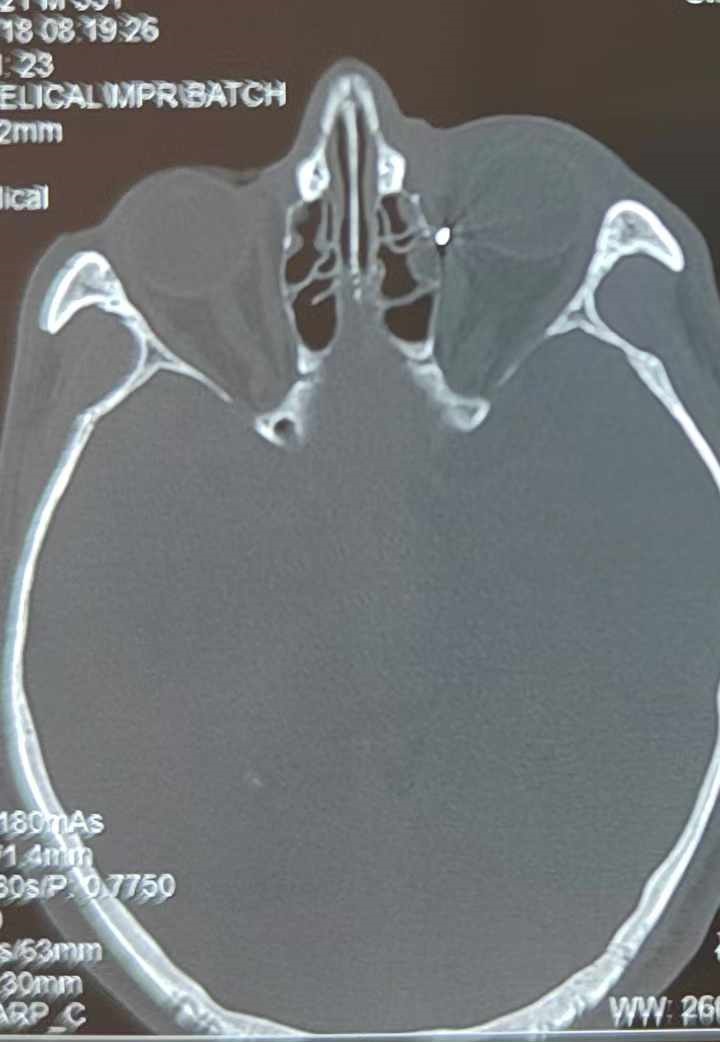

裝修工人高先生在作業(yè)過程中不慎被砸傷左眼,送至廈門眼科中心救治時(shí),眼外傷及眼底病2科副主任醫(yī)師李海波博士在CT檢查報(bào)告中發(fā)現(xiàn),進(jìn)入眼內(nèi)的異物在眶尖極為隱匿的位置,想要“不動聲色”地取出來,有些難度。

從CT報(bào)告中可以看出,高先生眼內(nèi)的異物不是很大,但位于眼窩深處,緊鄰鼻骨,從CT影像判斷應(yīng)該是金屬或合金異物。一般臨床上遇到這樣的情況,醫(yī)生會建議“保守觀察”,若異物傷及神經(jīng)、發(fā)生炎癥感染等,則需到條件較好、有眼眶病和眼外傷專業(yè)醫(yī)師的醫(yī)院進(jìn)行二期眶內(nèi)異物取出術(shù)(2021年《中國眼眶異物診斷和治療專家共識》)。

手術(shù)十分順利,李海波博士設(shè)計(jì)好了取出路徑,用這根細(xì)磁棒取出了一個(gè)米粒大小的鐵屑,過程中未造成二次傷害和大創(chuàng)面?zhèn)?。術(shù)后CT檢查顯示,高先生眼內(nèi)再無異物,他此時(shí)才松了一口氣。